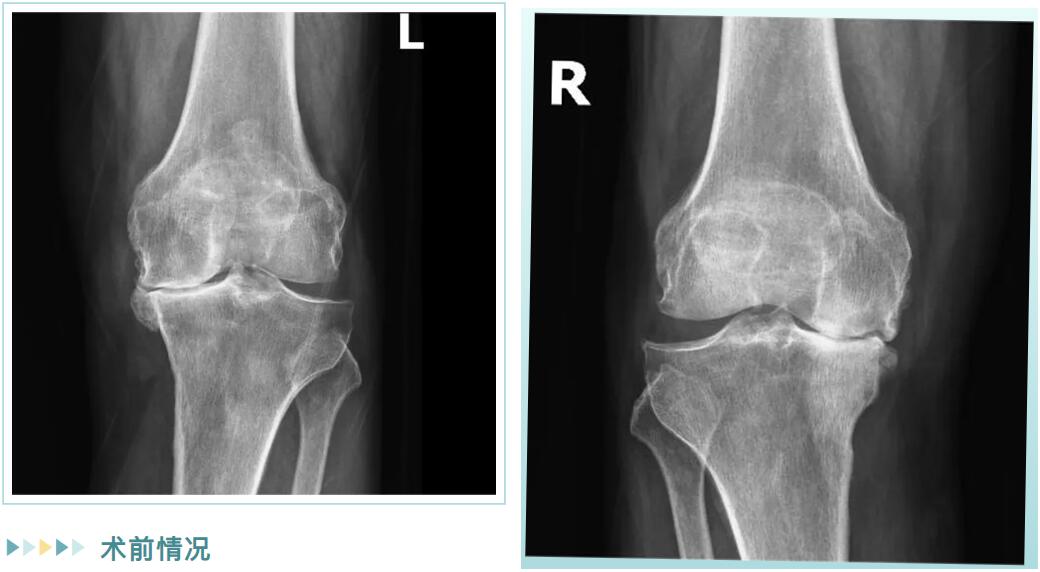

經詳細檢查,邵阿伯被診斷為“雙膝重度骨性關節(jié)炎”。在保守治療無效后,羅院長團隊為他量身定制了治療方案:雙側膝關節(jié)內側單髁置換術。

術前情況